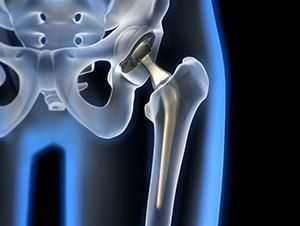

Рентгенография тазобедренного сустава

Тазобедренный сустав является сложным многоосным сочленением, которое выполняет сгибание/разгибание, отведение/приведение, пронацию и супинацию бёдер и принимает на себя серьёзную нагрузку. Любые нарушения в его функционировании не только приводят к серьёзному дискомфорту для человека, но и могут стать причиной развития серьёзных нарушений. Рентген тазобедренного сустава (ТБС) — это неинвазивный диагностический метод, ценность которого сложно переоценить.

Он нашёл широкое применение в разных областях медицины, включая травматологию, ревматологию, ортопедию, гнойную хирургию для диагностики заболеваний и последствий перенесённых травм, для определения объёма предстоящей операции или эффективности проведённого лечения. Процедура достаточно безопасна, высокоэффективна и проста, но при этом позволяет получить ценные данные о состоянии ТБС пациента.

Проведение рентгенографии ТБС

Стандартная рентгенография тазобедренного сустава проводится в 2-х проекциях. Помимо прямой используют вспомогательную, которая может быть боковой или задней косой, предусматривающей отведение бедра. Выбор, в данном случае, зависит от целей исследования и характера нарушений у пациента.